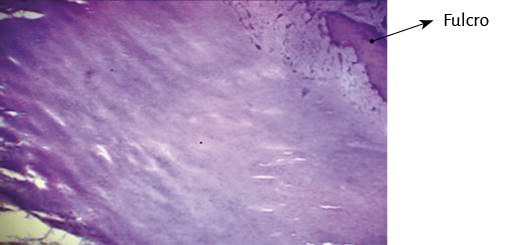

Análisis anatómico e histologíco del miocardio. En la secuencia del análisis histológico del miocardio desplegado (figura 27) se demuestra la orientación longitudinal, de acuerdo con la continuidad de los segmentos que tiene su conformación espacial, tanto en la cara interna como en la externa en cada uno de ellos. Las fibras tienen direcciones paralelas en ambas superficies (interna y externa) de cada uno de los segmentos. La superposición de los segmentos que implica la conformación helicoidal resulta indispensable para lograr la torsión miocárdica, acción fundamental de la mecánica cardíaca que no sería posible con la estructura de malla (entrecruzamiento de fibras miocárdicas). En esta estructura helicoidal se produce un rozamiento en sus superficies de contacto, lo que implica que presenten un sistema lubricante que facilita la movilidad autónoma de ellos con menor gasto de energía, tema que se analizará en esta Proposición.

Figura 27. Secuencia segmentaria del análisis histológico del miocardio continuo. Técnica de hematoxilina-eosina (15x).

Ningún segmento de la histología secuencial en la continuidad longitudinal del miocardio en nuestras investigaciones presentó una disposición en malla. En la cara externa de la parte distal del segmento descendente, al girar a nivel del ápex y transformarse en ascendente, los miocardiocitos generan en los cortes planimétricos una arquitectura disímil a la cara interna en su orientación, único sitio donde sucede esta situación. Esta disposición se halla dada en el ápex, en donde el trayecto en espiral de las fibras miocárdicas que se desplazan desde la periferia hacia el centro determinan un cambio brusco de la dirección, ya que las fibras subepicárdicas se vuelven subendocárdicas (figura 27), superpuestas como las tejas en un techo, que es lo que evidencia la imagen comentada. Esta configuración es lógica para la demostración de la disposición helicoidal pues sucede en el sitio donde el miocardio transforma en forma brusca su dirección de descendente en ascendente. En el resto la disposición es siempre paralela. El miocardio continuo se asemeja a la cinta de Moebius dado el cambio progresivo de la angulación en las fibras transformándose de epicárdicas en endocárdicas (164).

El miocardio es un músculo continuo y helicoidal; tal es el resultado de su disección. La función cardíaca no se puede explicar con una conformación en malla. Al respecto, el trabajo de Maclver (98) expresa: “Ninguno de los estudios histológicos del miocardio que conocemos, por el contrario, ha proporcionado ninguna evidencia de un origen e inserción como se describe para la supuesta banda miocárdica única […] Ninguna de estas investigaciones ha proporcionado ninguna evidencia de una alineación de los cardiomiocitos que sigue el curso de la banda miocárdica única”. En primer lugar, el fulcro cardíaco que hemos investigado en corazones humanos y animales describe el apoyo cardíaco, el que a través de las pruebas que requería Maclver daría pie a la disposición muscular única, continua y en hélice que presenta el miocardio. Con respecto a la segunda conclusión de dicho autor, en la secuencia del análisis histológico del miocardio desplegado se demuestra la orientación longitudinal, de acuerdo con la continuidad de los segmentos que tiene su conformación espacial, tanto en la cara interna como en la externa de cada segmento. Dichas orientaciones resultan paralelas en ambas superficies (interna y externa) en cada uno de ellos. Ningún segmento de la histología secuencial en la continuidad longitudinal del miocardio presenta una disposición en malla. En la cara externa de la parte distal del segmento descendente, al girar a nivel del ápex y transformarse en segmento ascendente, los miocardiocitos generan en los cortes planimétricos una arquitectura disímil a la cara interna en su orientación, único sitio donde sucede esta situación dado su cambio brusco de dirección (figura 27), evidencia fundamental del helicoide cardíaco.